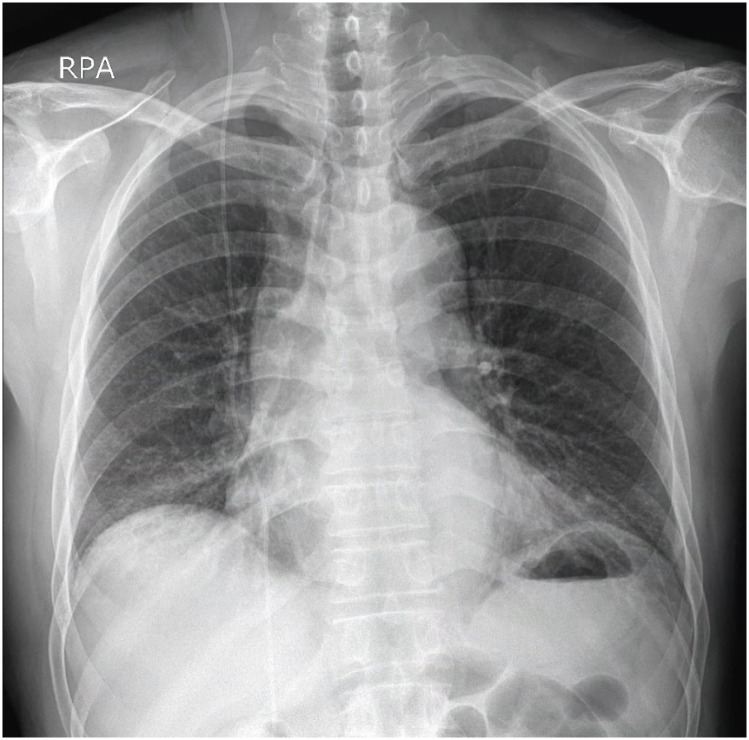

The treatment of hydrocephalus with a ventriculoperitoneal (VP) shunt can lead to complications such as shunt migration. A 67-year-old male, who had previously undergone VP shunt surgery for normal-pressure hydrocephalus, presented approximately five years later with symptoms of general weakness and abdominal pain. Imaging revealed shunt malpositioning, with the catheter passing through an abnormal route to the heart. The catheter was successfully removed under fluoroscopic guidance while monitoring patient's electrocardiogram to prevent potential secondary complications. Although rare, cardiac migration of VP shunts can lead to life-threatening secondary complications. Our case highlights the possibility of delayed upward migration of the shunt catheter in patients with VP shunts, emphasizing the need for various strategies to address and manage this issue.

Abstract Image